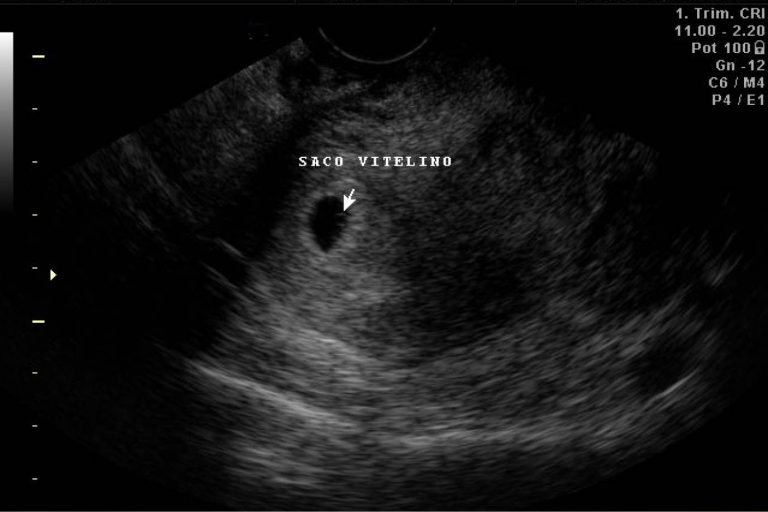

MEDIDA DEL SACO GESTACIONAL POR ULTRASONIDO YouTube

Existen varias razones por las cuales el embrión puede no ser visible en la ecografía a las 6 semanas de gestación: Desarrollo temprano: A las 6 semanas de embarazo, el embrión aún está en una etapa de desarrollo muy temprana. Es posible que sea demasiado pequeño para ser detectado por la ecografía. Ubicación del embrión: El embrión.. El saco gestacional es una de las primeras estructuras que puede ser detectada mediante la ecografía. Si te preguntas cuándo se ve el saco gestacional en una ecografía, se puede detectar mediante el ultrasonido endovaginal entre la semana 4 y la semana 5 de embarazo, cuando la estructura apenas mide de 2 a 5 milímetros de diámetro.Se observa como una pequeña esfera de líquido, con.